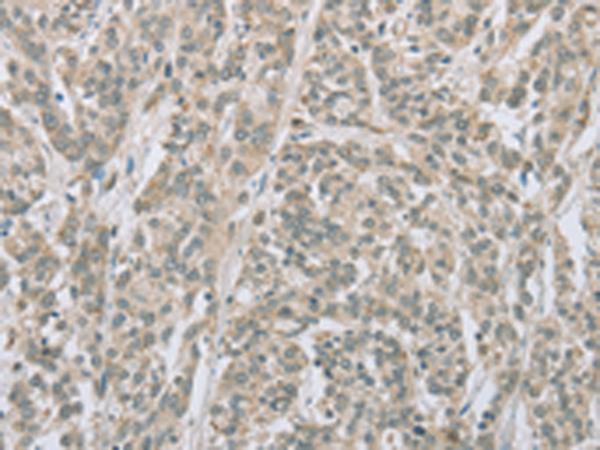

分类: 科研抗体货号: P08265别名: DEL1应用: WB,IHC反应种属: Human, Mouse